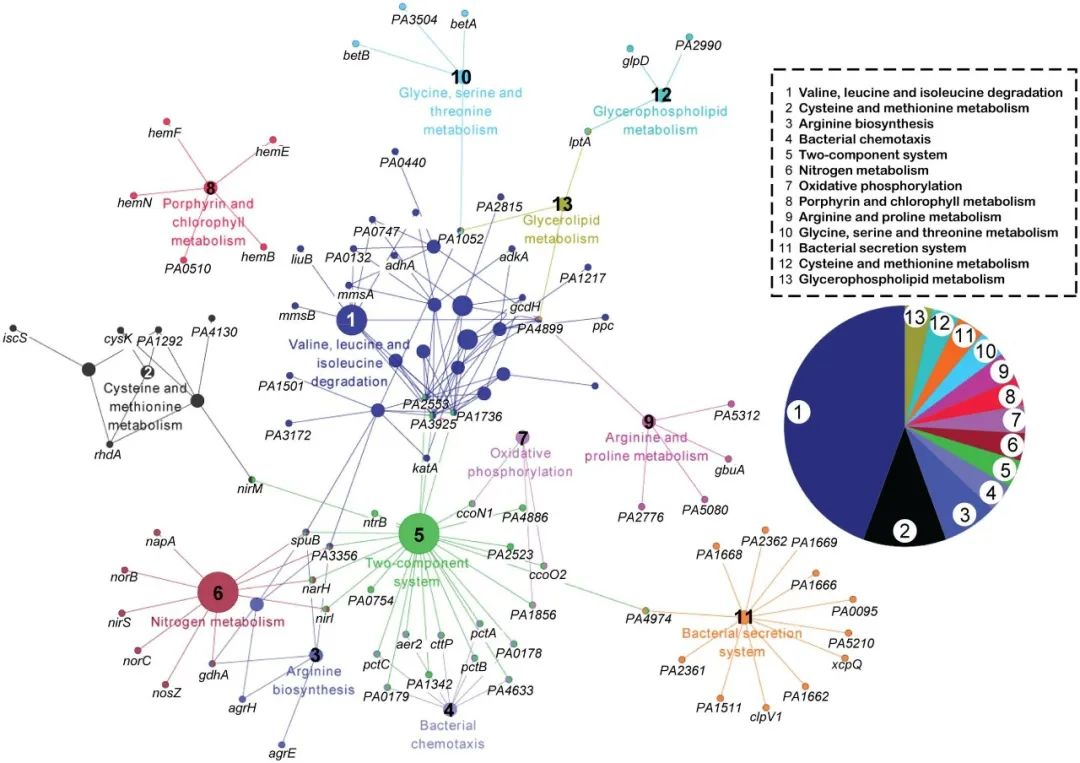

滑动查看更多 点击查看大图

期刊封面图设计

滑动查看更多 点击查看大图

论文图表排版

滑动查看更多 点击查看大图

论文图表美化

滑动查看更多 点击查看大图

数据分析与作图

滑动查看更多 点击查看大图

我们的数据分析人员全部来自清华、北大、中科院、协和、NIBS等国内顶尖研究机构,均发表过高分SCI论文,非常擅长生物、医学等领域各类型数据的分析与作图,可以完成基因组学、转录组学、蛋白质组学、代谢组学、表型组学、多组学、GEO和TCGA等数据库挖掘、临床病例数据分析、Meta分析、分子模拟与对接等各种数据分析与作图的项目。他们优秀的学术背景,保证了他们一流的分析水准。